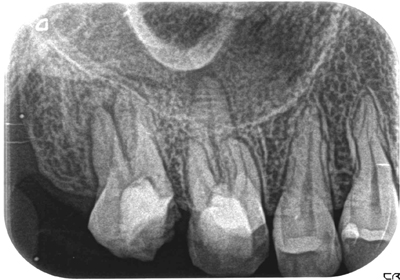

症例1【30代女性】右上7番根尖相当部に大きな病巣がみられ、副鼻腔の粘膜にも波及し、肥厚している。15ヶ月後、病巣はほぼ消失し、骨が再生、副鼻腔粘膜の肥厚も消失。

治療前